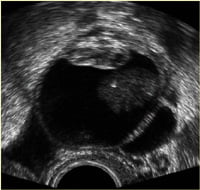

Genelde rutin muayene ya da başka bir sebepten dolayı yapılan muayene ve ultrasonografide saptanırlar. Muayenede hastanın yaşı, kitlenin büyüklüğü, şekli, saf kist ya da solid yapıda oluşu, etrafa yapışık olup olmadığı, hassasiyet olup olmadığı, Önemlidir. Ultrasonografide saf kist görünümünde olan ve 5-6 santimden küçük çapta olan kistlerin iyi huylu ve fonksiyonel olma olasılığı yüksektir.Ayrıca tanıda hastanın ve kitlenin durumuna göre tomografi, manyetik rezonan hormon tetkikleri ve kanda tümör belirteçleri incelenir ve tedavi için bir karara varılır.